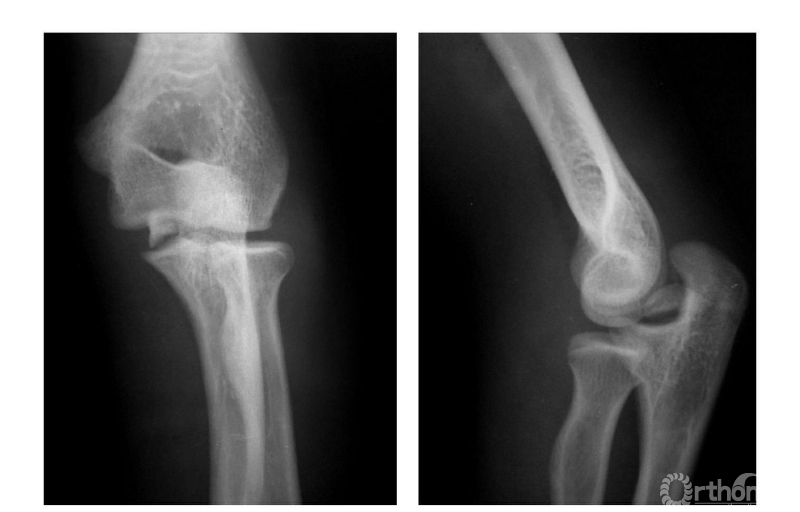

例2:内上髁骨骺并带内髁骨块向外翻转移位,达关节水平(图5)。

图5

Ⅲ度损伤:

例1:内上髁骨骺撕脱并移至尺肱关节间(图6)。

图6